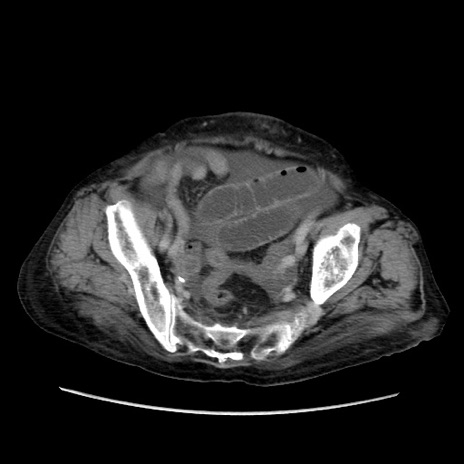

症例31(横断像)

【症例】80歳代 女性

【主訴】腹部膨満感

【現病歴】他院にて肝硬変にてフォロー中。1週間前から便秘、腹部膨満感、臍部腫瘤あり受診となる。

【既往歴】肝硬変

【身体所見】腹部膨隆あり、皮膚変化なし、疼痛なし。

【データ】WBC 4600、CRP 0.25